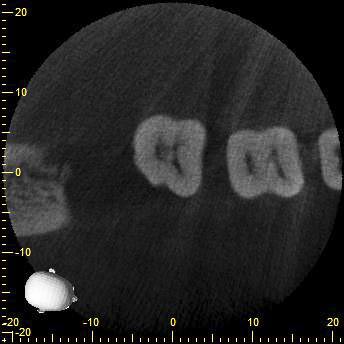

KD47-2

Und das hier war einfach nur Pech…